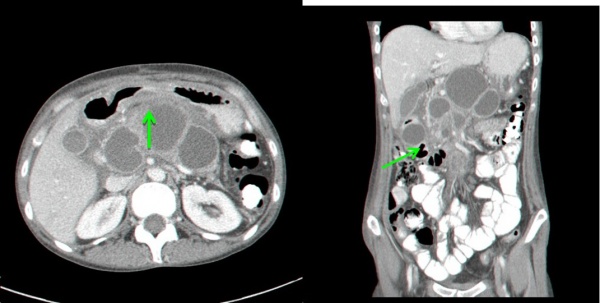

- טומוגרפיה ממוחשבת – נראה באיזור הלבלב גוש או גושים בד"כ בעלי גבולות ברורים המכילים בתוכם נוזל (תצלום 4.9).